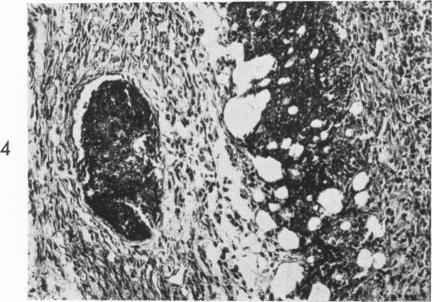

Hyperacute allergic encephalomyelitis. Lymphatic system as site of adjuvant effect of pertussis vaccine.

Am J Pathol. 1967 Mar;50(3):465-83.

A HYPERACUTE FORM OF ALLERGIC ENCEPHALOMYELITIS.一种超急性形式的变应性脑脊髓炎。

Am J Pathol. 1965 Jul;47(1):61-88.